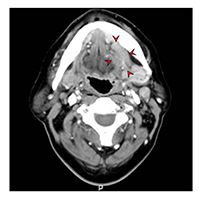

악골 및 연조직의 진단에 사용합니다. 악성 여부에 대한 영상학적 진단, 침범 범위 및 전이여부 등을 알아보기 위한 검사입니다. 임상적 병기 진단에 자기공명영상(MRI)와 더불어 주로 사용되며 수술 가능여부 및 수술 범위 결정 등에 기본적으로 필요한 검사입니다. 초음파 검사와 함께 생검시 종양으로의 정확한 접근을 위하여 사용되기도 합니다. 혈관과 림프선의 구분, 종양의 경계부 확인 등을 위하여 조영제를 사용합니다.

![[좌측 설암 전산화단층촬영 이미지]](../res/images/cancer/21_2_3.jpg)

[좌측 설암 전산화단층촬영 이미지]